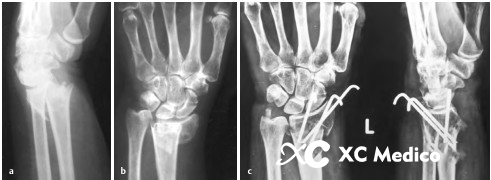

3. Если вход и точки выхода Киршнера очень близки к перелому, может произойти сбой фиксации. Два спинных провода Kirschner не должны проходить через пальмовую кору на том же уровне, а точка выхода из ладони должна находиться в 2 см от места перелома. См. Рисунки AC ниже.

4. Когда дорсальная кора чрезвычайно заправлена, постарайтесь не войти в место разрушения фрагмента дистальной кости, так как это может привести к неудаче фиксации. Рисунки AE ниже.